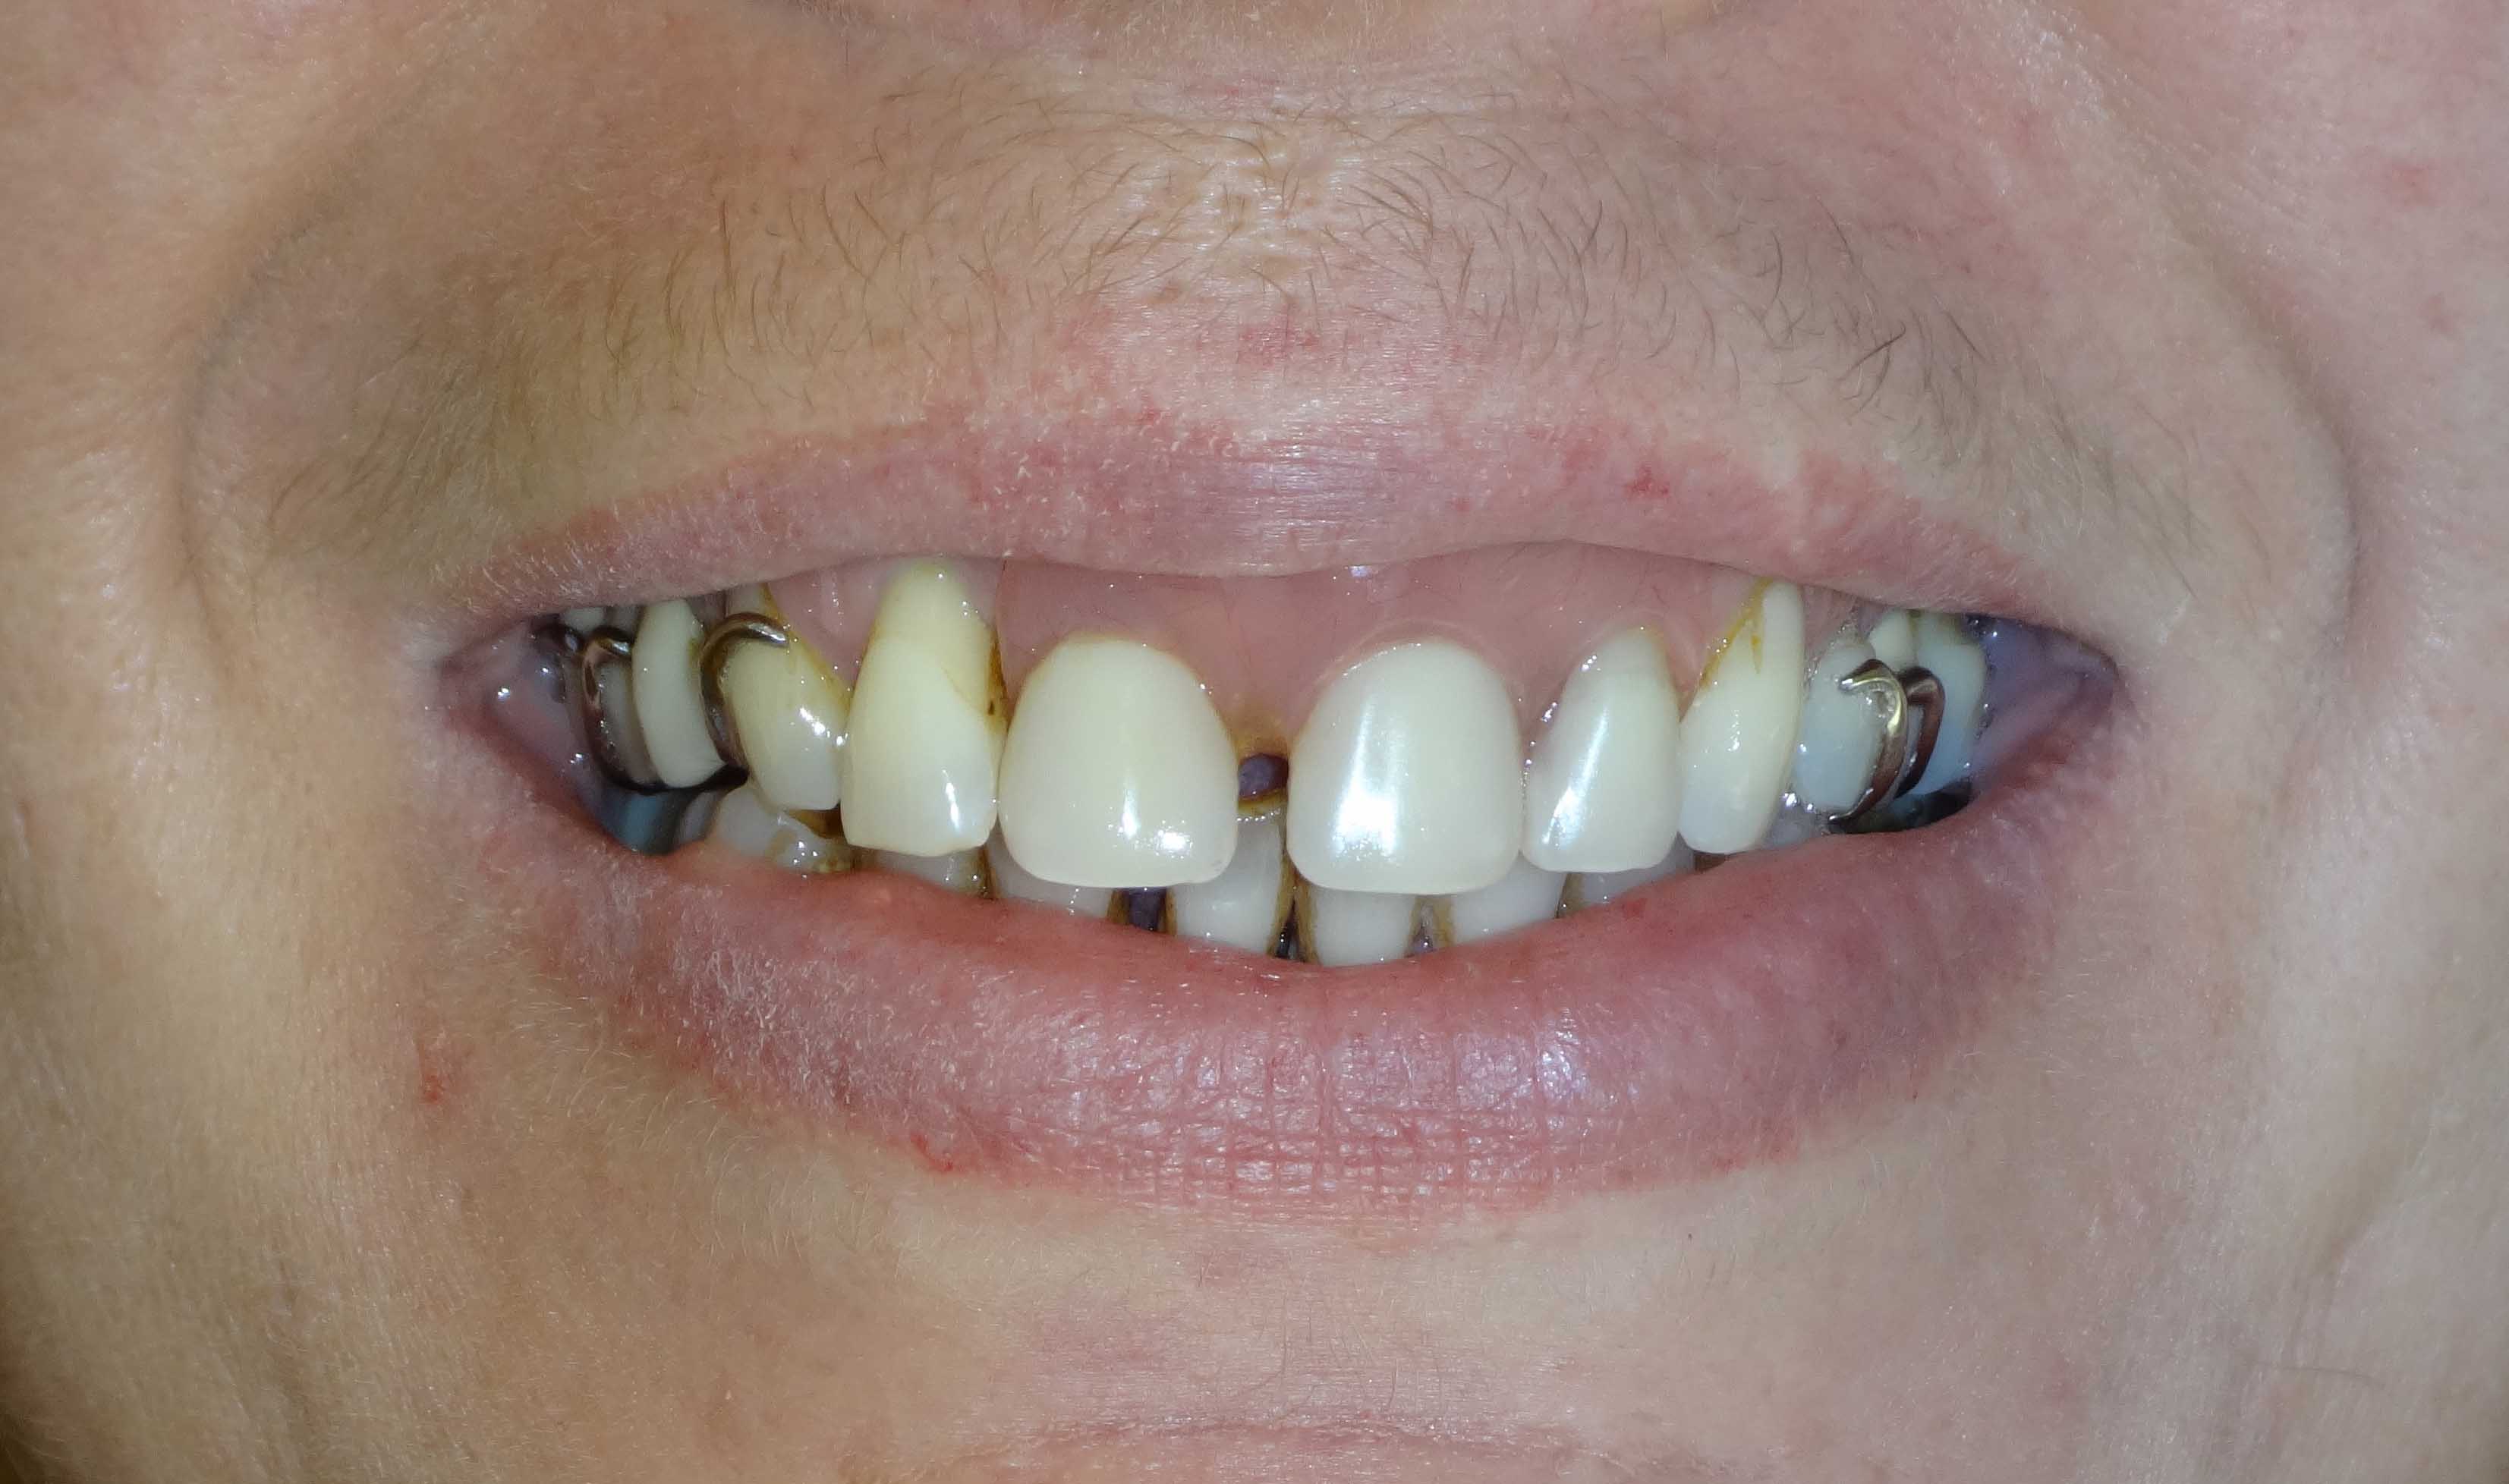

Les années passent avec toujours autant de cigarettes, et elle revient me voir en juillet 2017 avec un soucis esthétique au niveau de sa 12 plus les crochets du stellite qu'elle trouve très moches (et accessoirement 2 prémolaires en bas qui ne tiennent plus)

J'ai fait un partiel résine 5 dents mandibulaire, rajouté la 12 sur le stellite, fait le traitement paro non chirurgical pour assainir tout ça .

Elle ne veut pas de dents longues justement d'où les petites centrales sur le stellite, ni de zones noires entre les racines déchaussées...)

Et elle voudrait que les crochets disparaissent.